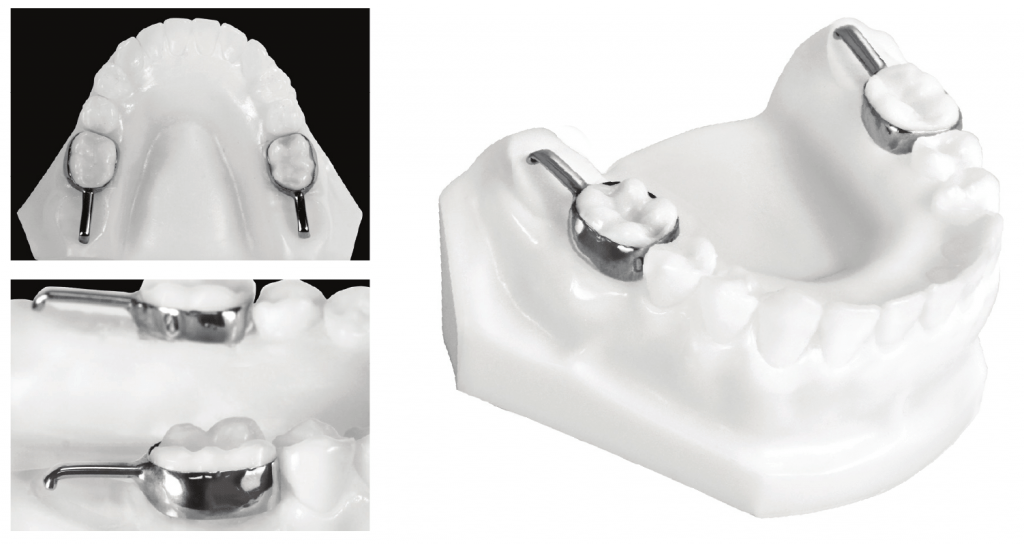

Band and loop – this device is most often used when the primary first molar is prematurely lost unilaterally. The second molar is banded, with the loop sitting against the distal surface of the canine. The band and loop is removed once the first premolar starts erupting. It can be used on other teeth. The most common reason stated for the failure of the appliance is cement failure and solder breakage. Crown and loop space maintainer – similar to a band and loop design but it has a higher survival rate.

Distal shoe – a modification of the band and loop, where one tooth (usually the adult first molar) is unerupted or partially erupted.

Orthodontic wire or fiber reinforced resin bonded directly to teeth can act as an inexpensive and immediate solution.